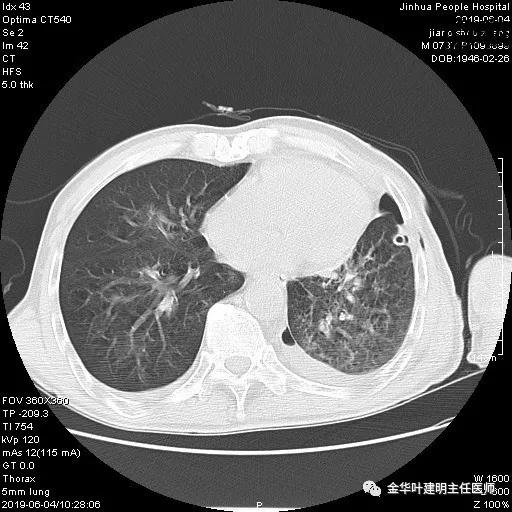

6.4上午:24小时引流出血性乳糜液1800毫升。是否再次手术进行右进胸胸导管结扎,抑或继续保守治疗非常纠结!压力非常大!!多方讨论会诊无法取得一致意见,但一般认为,引流量在1000毫升以上宜积极手术。情况与浙二医院范军强教授联系,请求指导,范教授认为左侧肺手术,损伤胸导管主干的机会较小,多数可保守治疗而愈。在他们的病例中,也有结扎胸导管后引流量仍无减少,效果并不能完全保证。建议可以考虑胸管夹管观察(因为淋巴管压力低,予以适当的压力,漏出量可能会明显减少),同时继续禁食,并静脉营养支持,引流管口可能会有渗液,注意更换敷料。与家属充分沟通后决定试夹管;这天血色素9.0 g/L;胸部CT复查示:

夹管情况下,于6.5复查胸片:

感觉左肺密度还可以,肺没有被全部压萎陷,积液有,但不是特别多。